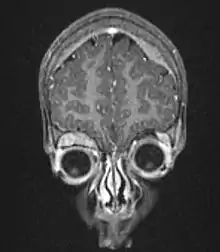

| Microscopic view of a typical neuroblastoma with rosette formation | |

On microscopy, the tumor cells are typically described as small, round and blue, and rosette patterns (Homer Wright pseudorosettes) may be seen. Homer Wright pseudorosettes are tumor cells around the neuropil, not to be confused with a true rosettes, which are tumor cells around an empty lumen.[27] They are also distinct from the pseudorosettes of an ependymoma which consist of tumor cells with glial fibrillary acidic protein (GFAP)–positive processes tapering off toward a blood vessel (thus a combination of the two).[28] A variety of immunohistochemical stains are used by pathologists to distinguish neuroblastomas from histological mimics, such as rhabdomyosarcoma, Ewing's sarcoma, lymphoma and Wilms' tumor.[29]